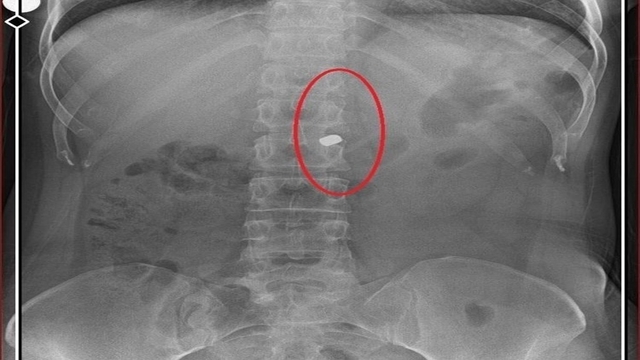

Osmangazi ilçesi Küplüpınar Mahallesi'nde 2023 Haziran ayında meydana gelen olayda; İlyas Sarıkaya, mahalleden arkadaşı Recep Özaslan'ı, Alzheimer hastası annesi A.S. ve sevgilisi Fatma O. ile birlikte yaşadığı eve çağırdı. İddiaya göre; uyuşturucu etkisinde olan Sarıkaya, sevgilisiyle ilişkisi olduğunu düşündüğü Özaslan'ı tabancayla vurdu ardından da 'acı çekmesin' diye 2 kez daha ateş etti. Özaslan, beline ve göğsüne isabet eden kurşunlarla hayatını kaybetti.

İlyas Sarıkaya, sevgilisi Fatma O.'yu da 8 kurşunla vurup, yaraladı. Arkadaşı Özaslan'ın cesedini önce çarşafa sonra da streç filme sarıp bantlayan Sarıkaya, eczaneden aldığı sargı bezi ve ilaçlarla pansumanını yaptığı sevgilisine yaralı haldeyken 21 gün boyunca cinsel saldırıda bulundu.